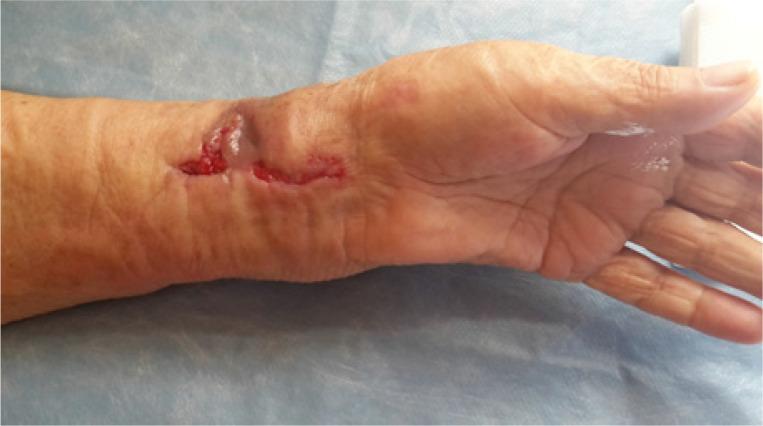

An aggressive course of pyoderma gangrenosum mimicking bacterial osteomyelitis after open reduction and internal fixation of a distal radius fracture with a titanium plate.

Pyoderma gangrenosum (PG) is a rare condition characterized by the development of aseptic, non-healing skin ulcers. Any skin trauma, such as a surgical incision, can trigger an outbreak of lesions. Our case and literature review show that a physician should consider PG in every event of a non-healing, aseptic wound after surgery. The treatment of PG requires collaboration within a multidisciplinary team and immunosuppressive therapy is the first line of treatment, while surgical interventions should be avoided in the active stage of PG.